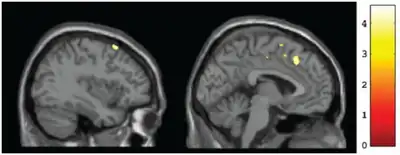

Structural abnormalities of the brain are observable, physical damage to the brain or brain structures caused by prenatal alcohol exposure. Structural impairments may include microcephaly (small head size) of two or more standard deviations below the average, or other abnormalities in brain structure (e.g., agenesis of the corpus callosum, cerebellar hypoplasia).[16]

Microcephaly is determined by comparing head circumference (often called occipitofrontal circumference, or OFC) to appropriate OFC growth charts.[22] Other structural impairments must be observed through medical imaging techniques by a trained physician. Because imaging procedures are expensive and relatively inaccessible to most people, diagnosis of FAS is not frequently made via structural impairments, except for microcephaly.